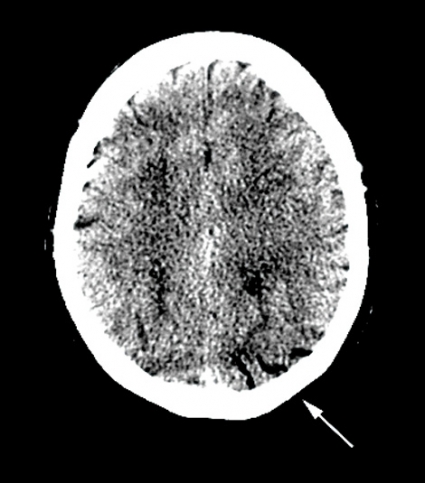

Vid litteratursökning senare samma dag återfanns ett mycket snarlikt fall av cerebral luftembolisering [1]. DT-undersökningarna granskades på nytt. Som tidigare nämnts fanns luft intrahepatiskt, men den här gången noterades luft även i vena femoralis på höger sida (Figur 2) samt i mindre kärl i glutealregionen på höger sida och i båda sidors ovarikakärl. Misstanke fanns även om luft i mesenterialkärlen. På DT av skallen återfanns intrakraniellt belägen luft i flera kärl, främst parietooccipitalt på vänster sida (Figur 3) men även högt frontalt bilateralt.